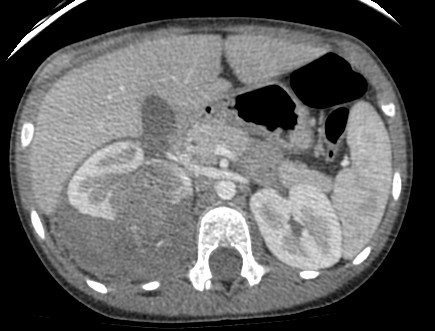

TC:

- Tumor heterogéneo con densidad de tejidos blandos que puede contener calcios (< 10%) y también áreas de grasa (nota: el angiomiolipoma es muy infrecuente en pediatría).

- El realce es parcheado y permite mejor definición y determinación de las relaciones del tumor.

- Las metástasis pulmonares son las más frecuentes en el momento del diagnóstico.